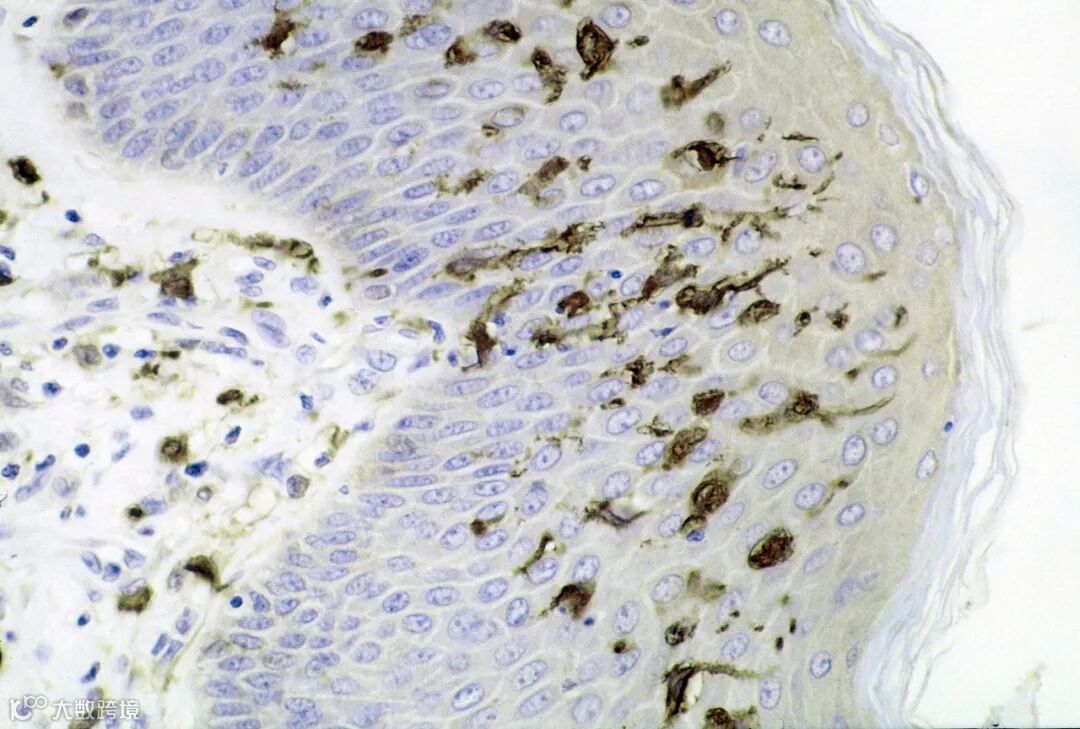

树突状细胞是人体免疫系统中的“司令官”或“哨兵”细胞,专职捕捉和呈递抗原信息。当体内出现癌细胞等异常时,DC会摄取其独特抗原片段,并将这信息“呈递”给淋巴细胞(主要是T细胞),从而启动针对性的免疫攻击。然而,在很多晚期癌症患者体内,DC功能可能不足或肿瘤伪装性太强,导致免疫系统未能及时识别癌细胞。DC疫苗疗法的思路就是体外培养和训练患者自身的树突状细胞:从患者血液中提取单核细胞,在实验室条件下诱导其成熟为树突状细胞,并加载上特定的“肿瘤抗原”信息,令其记住癌细胞的特征。随后,将这些“训练完毕”的DC回输给患者,它们就会在体内寻访免疫系统的“战友”T细胞和NK细胞,将癌细胞的特征传达给后者,号召全体免疫细胞出击去清除含有该特征的癌细胞。通过这种方式,患者的免疫系统等于上了一堂“识别敌人”的强化训练课,能够对癌细胞发起更有效的定向打击。这种疗法精准且高度个体化,因为抗原通常来自患者自身的肿瘤或针对性的通用肿瘤抗原。

东京Midtown先端医疗研究所的DC疗法有几大特色使之处于国际先进水平。首先,他们采用了由大阪大学杉山教授团队开发的WT1肿瘤抗原特许技术来制造DC疫苗。WT1是一种在多种恶性肿瘤(包括白血病、胰腺癌等)中高度表达的肿瘤相关抗原。利用WT1抗原“脉冲”树突细胞,可以唤起针对癌细胞的强大免疫反应。这项技术在全球享有盛名,被证明能够有效激活以Th1型为主的细胞免疫反应(特点是大量产生抗肿瘤的IL-12等细胞因子)。研究所严格为每位患者定制合适的DC疫苗方案,包括优化树突细胞的亚型和抗原种类,以期最大限度地引发针对患者肿瘤的免疫攻击。其次,该疗法已有大量学术论文支持,临床基础扎实。研究所本身积累了丰富病例经验,部分晚期患者经过DC疫苗联合其他疗法后病情稳定甚至肿瘤缩小,为难治性癌症带来了希望。第三,研究所正积极推动此疗法进入日本先进医疗批准程序,力争将其纳入医疗保险覆盖范围,使更多患者负担得起。这种努力也从侧面体现了DC疗法在安全性和有效性方面的成熟程度。